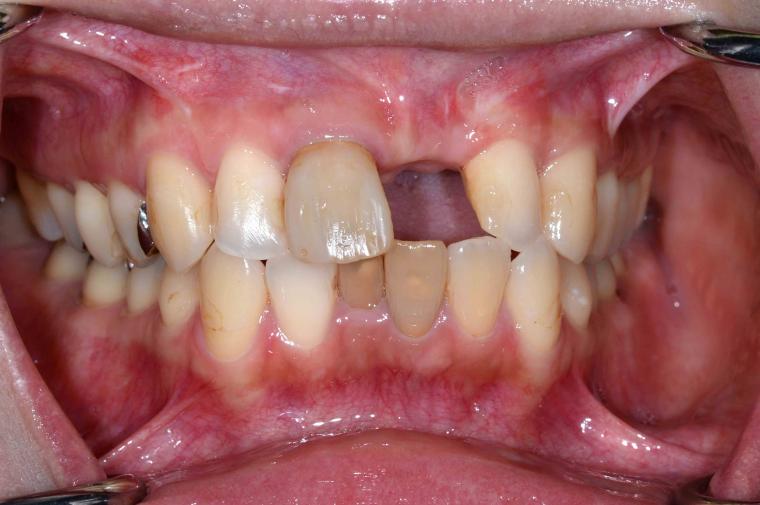

BEFORE

37歳女性/上1本欠損/インプラント埋込手術

左上前歯が脱臼した状態でご来院した患者さんです。

抜歯後に土台となる骨を作る処置の後、インプラントを1本埋入しました。